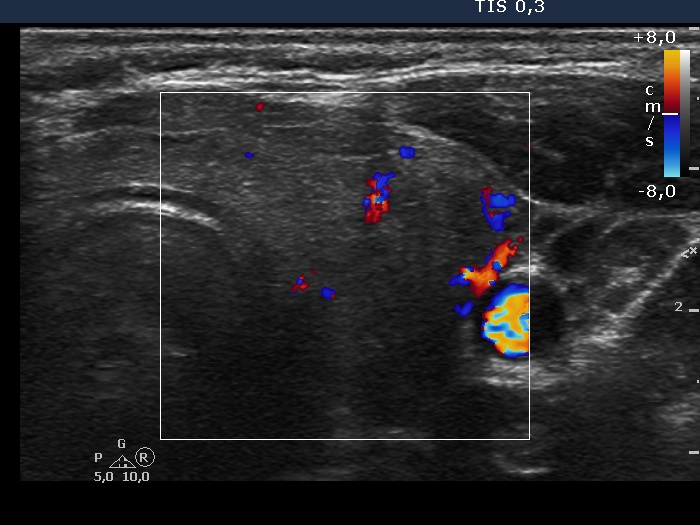

Right lobe, longitudinal scan

Left lobe, transverse scan, color Doppler mode. The vascularization is decreased.